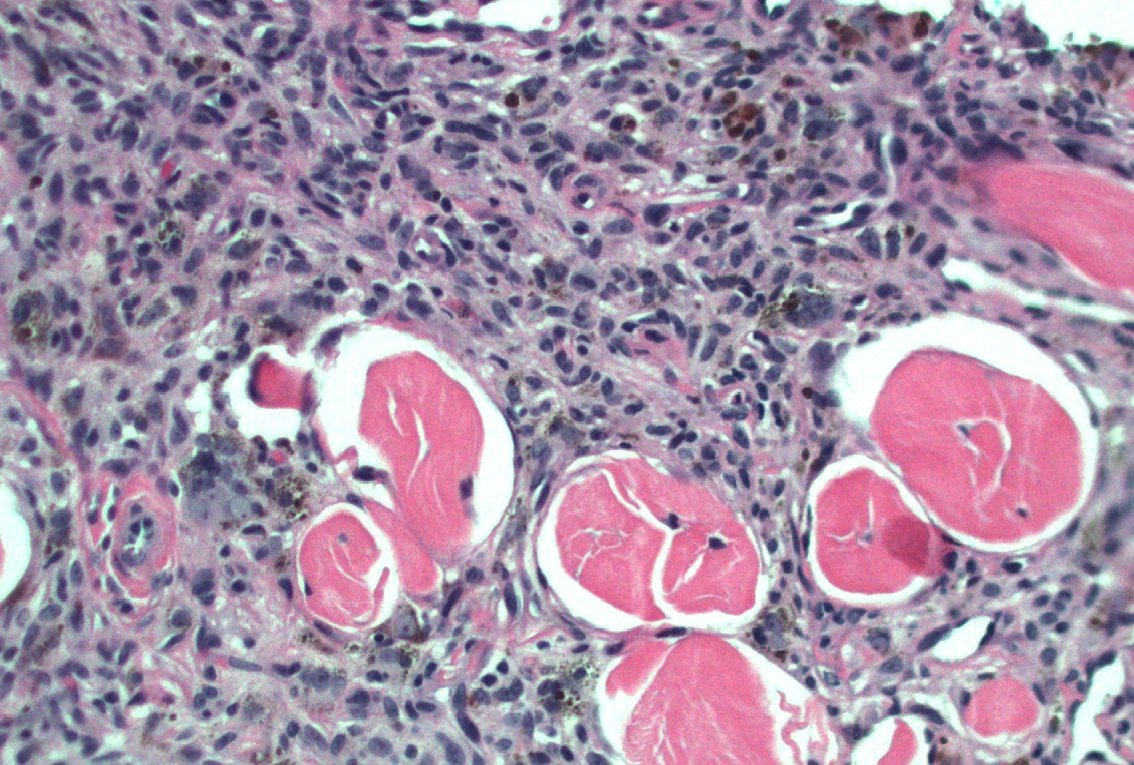

40 F. 10 cm deep thigh mass.

Answer ✅ youtu.be/QDb68_G1HR4?si…

Digital slide 🔬 kikoxp.com/posts/11800.

Differential dx: kikoxp.com/posts/12124

#BSTpath #pathologists #pathology #pathTwitter